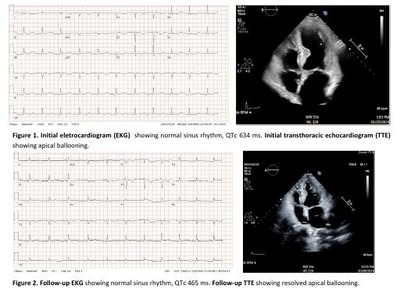

Case description: A 69-year-old female with a history of type 2 diabetes mellitus, and hyperlipidemia presented after a syncopal event. It was preceded by sudden onset of dizziness, nausea, and vomiting. She had been using berberine for a year to lower her blood sugar and had recently switched to a higher dose of a more potent formulation. Vitals were unremarkable. Initial evaluation revealed a prolonged QTc interval of 659 ms (Figure 1A) and elevated troponin-I levels. She was treated with intravenous magnesium, which improved her QTc to 540 ms and revealed new T-wave inversions in the precordial leads. Echocardiogram showed an ejection fraction (EF) of 35%, with LV apical akinesia and hypercontractile basal segments. Cardiac catheterization ruled out significant coronary artery disease, leading to a diagnosis of TCM. Berberine was discontinued, and guideline-directed medical therapy was initiated. Given the presentation with syncope and high suspicion of aborted sudden cardiac death (SCD), she was discharged with a wearable cardioverter-defibrillator (WCD) as a precaution due to the risk of ventricular arrhythmias during recovery. At her 8-week follow-up, QTc and EF had normalized (Figure 1B), prompting WCD removal.